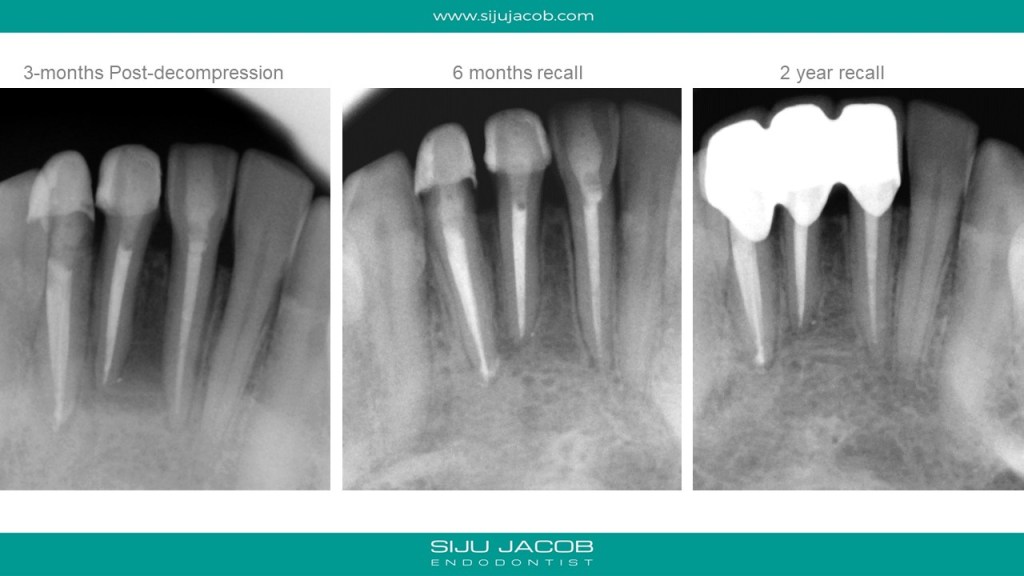

This case seemed to be responding well to conventional treatment. There wasn’t any drainage, so I obturated. The patient kept getting pain in the labial surface. So, we decided to do de-compression. The tooth reponded well to decompression and we saw very good healing at 6-months post de-compression. I saw this patient again 2 years later and someone meanwhile had gone and placed joint crowns on these teeth. Oh well….